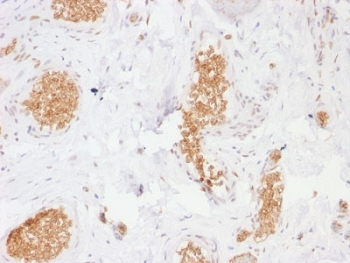

IHC staining of FFPE human ovarian carcinoma tissue with SLC2A1 antibody (clone GLUT1/7308). Inset: PBS used in place of primary Ab (secondary Ab negative control). HIER: boil tissue sections in pH9 10 mM Tris with 1 mM EDTA for 20 min and allow to cool before testing.

| Dilution range | Immunohistochemistry (FFPE): 1-2ug/ml for 30 min at RT |

| Description | Recognizes a protein of 55kDa, which is identified as GLUT-1. Glucose transporters are integral membrane glycoproteins involved in transporting glucose into most cells. There are many types of glucose transport carrier proteins, designated as Glut-1 to Glut-12. Glut-1 is a major glucose transporter in the mammalian blood-brain barrier. It is expressed in high density on the membranes of human erythrocytes and the brain capillaries that comprise the blood-brain barrier. Glut-1 is expressed at variable levels in many human tissues. Overexpression of Glut-1 has been linked to tumor progression or poor survival of patients with carcinomas of the colon, breast, cervical, lung, bladder and mesothelioma. Glut-1 is a sensitive and specific marker for the differentiation of malignant mesothelioma (positive) from reactive mesothelium (negative). |